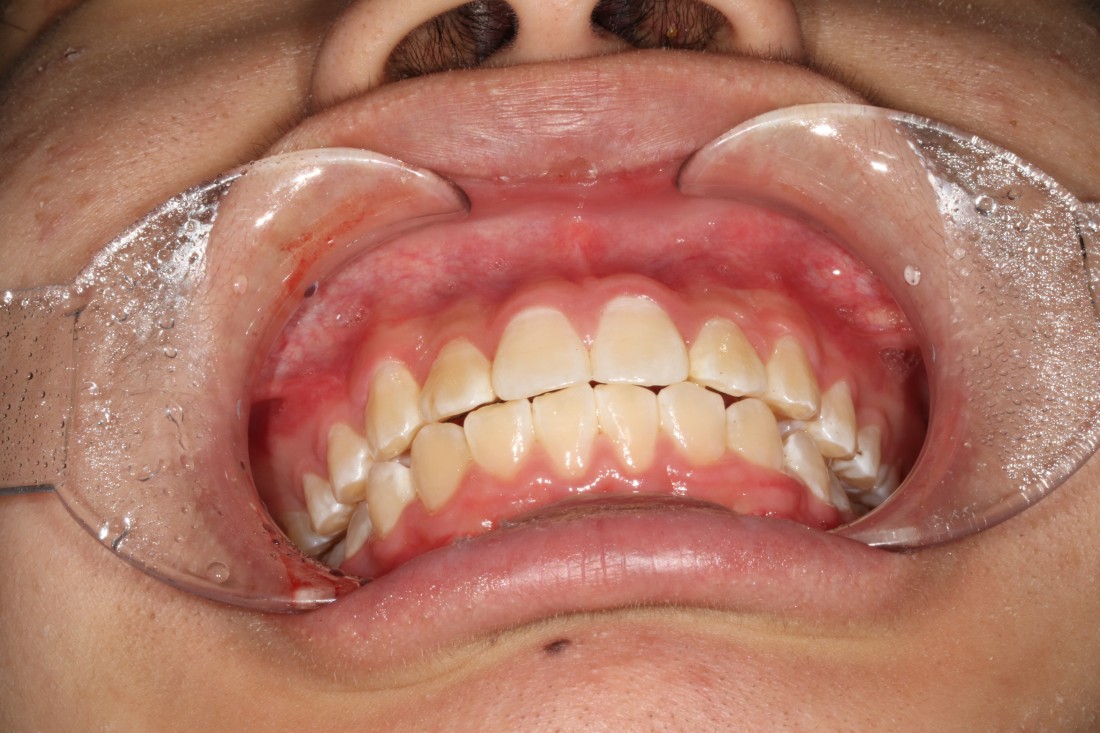

교정 진료는 1년 이상의 기간이

소요될 정도로 오랜 시간을 두고

천천히 변화하는 과정을 관찰하며

교정전문의와 고객간의 의견조율로

최상의 치료결과를 얻을 수 있는데요.